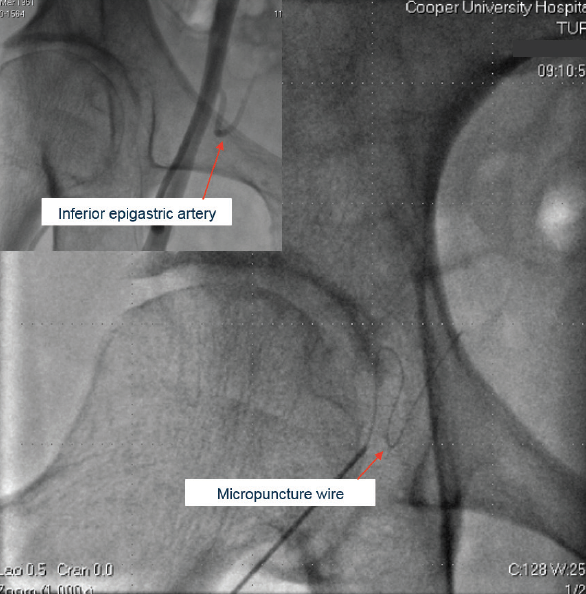

Figure 2. The case for fluoroscopy of the wire prior to sheath advancement. The micropuncture wire has been advanced and does not appear to follow the standard path of the external iliac artery. The wire was withdrawn and readvanced, a sheath was placed, and contrast was then injected (upper left inset). As clearly shown, the wire had been in the inferior epigastric artery. Sheath advancement would almost certainly have led to perforation and probably retroperitoneal hemorrhage.

• Fluoroscopy of guidewire advancement prior to withdrawing the needle and placing sheath to confirm that the wire is in the external iliac artery (and not the inferior epigastric or lateral circumflex of the hip or other branch arteries) (Figure 2)